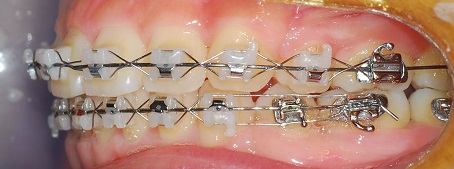

측면사진

그거 말씀 드렸더니 치아도 흔들리고 그래서 그 뒤쪽 사랑니앞에 어금니만 와이어를 끊어내고

당분간 아프지 않을 때까지는 그쪽 이로 씹는 것도 자제 해야 한다고 하셨어요.